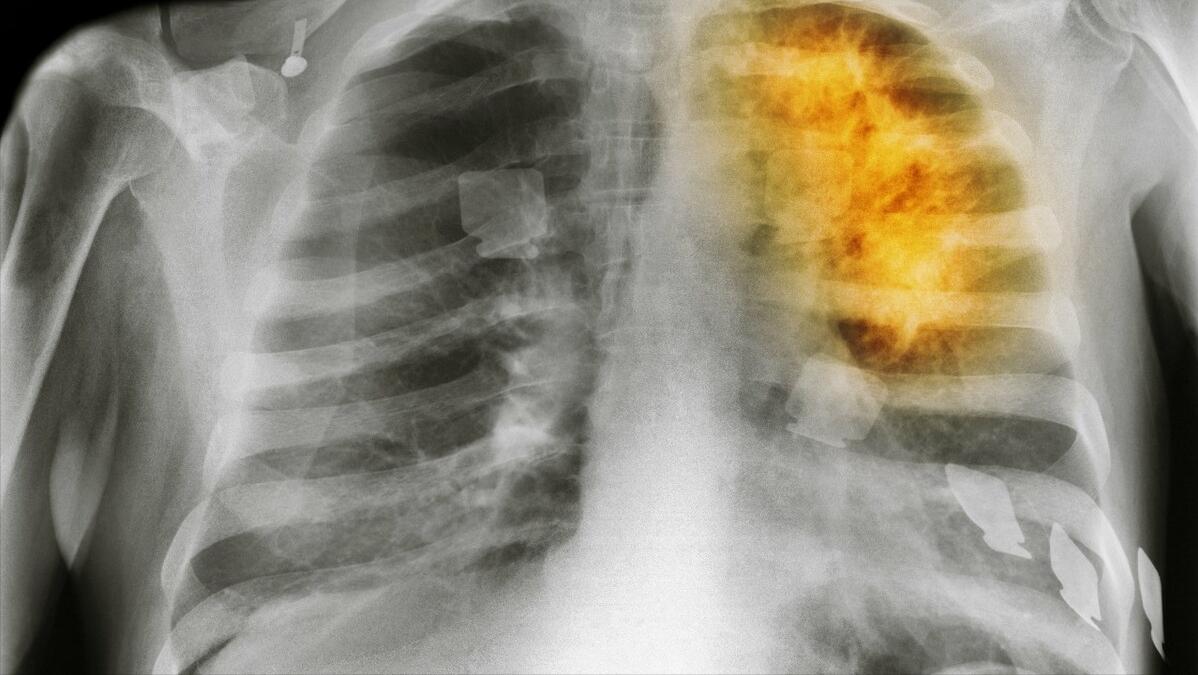

另外一个导致很多儿童驼背的一个原因,可能是脊柱结核。这种疾病是由于肺结核、消化道结核、淋巴结核等疾病扩散感染到脊柱造成的。发病也是比较缓慢,发病时会出现低烧、食欲减退、疲倦等症状,儿童则常会在夜间出现啼哭、呆滞的症状。

由于胸廓发生变形、胸腔容量随之减小,呼吸也会受到限制,影响肺功能的正常运行及呼吸的通畅,可能会增加驼背者患肺炎、肺气肿等疾病的风险。